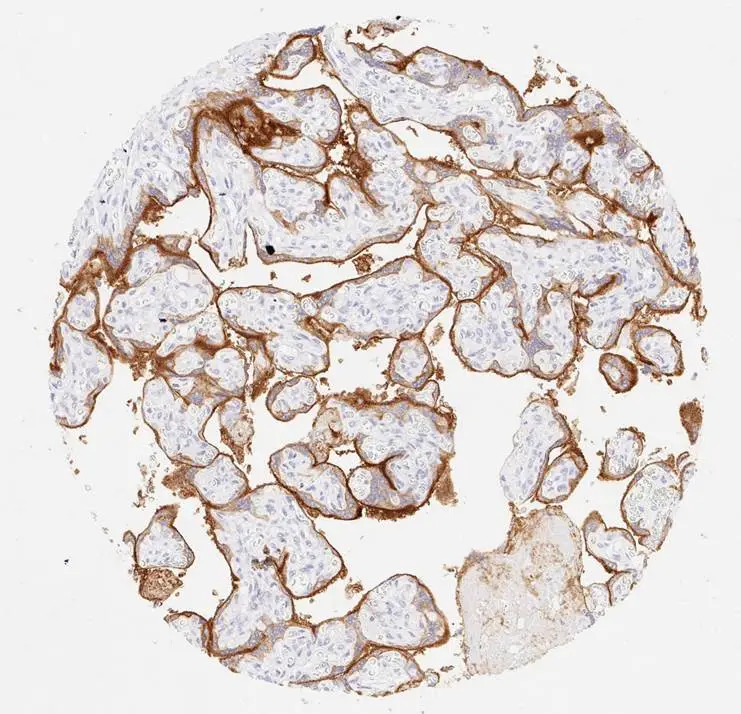

IHC-P analysis of human placenta (mature) tissue using GTX639925 PD-L1 antibody [H302] HistoMAX™.

Strong PD-L1 staining of the external membrane of the syncytiotrophoblast.